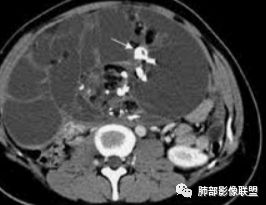

水晶石头:患者老年男性,发现皮肤粘膜黄染5天,右肺占位1天。

胸部CT:右肺中叶内侧段紧邻心脏实性结节,边缘光滑,边界清楚,宽基底与胸膜相连,内可见不规则钙化,钙化内见点状低密度影,增强中度强化,综合考虑良性病变。畸胎瘤可能大,鉴别胸膜孤立性纤维瘤及胸腺瘤。

王秀仙:右侧前纵隔肿块,边缘分叶,周围肺组织推移,宽基底与纵隔胸膜相连,可见胸膜尾征,密度不均,病灶中心可见斑块状钙化,右侧内乳动脉位于病灶前外侧并略增粗,实性成分明显强化,考虑纵隔畸胎瘤,鉴别胸腺瘤。

蓝天白云:定位纵隔,病灶呈实性成分,内见钙化,钙化位于病灶中心,实性成分均匀延迟强化,考虑良性病变,如果胸膜起源考虑sft,纵隔来源胸腺瘤,鉴别畸胎瘤。黄勇老师说过右侧心膈角区可以发生胸腺瘤

三个石头:前纵隔占位,不规则分叶肿块,内斑片状,点状钙化,内乳动脉增粗,肿块延迟强化。考虑良性占位,疾病谱畸胎瘤,胸腺瘤,巨淋。

右侧前纵膈肿块,边缘分叶,病灶中心可见斑块状钙化,实性成分明显持续强化,考虑胸腺瘤。

右前纵隔不规则肿块,分叶状,内见斑块状钙化,肺组织受压内移,胸膜抛起,胸膜下纵隔脂肪间隙不清,增强后轻度强化,右侧内乳动脉无明显增粗,定位于纵隔内,定性:畸胎瘤与胸腺瘤鉴别,形态不规则,分叶,钙化明显,右侧内乳动脉不粗,畸胎瘤可能>胸腺瘤。